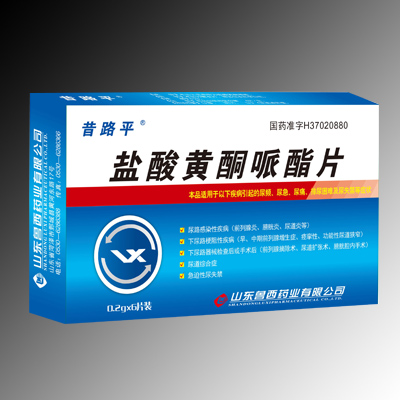

鹽酸黃銅呱酯片

鹽酸黃銅呱酯片 -

鹽酸黃酮呱酯片

鹽酸黃酮呱酯片